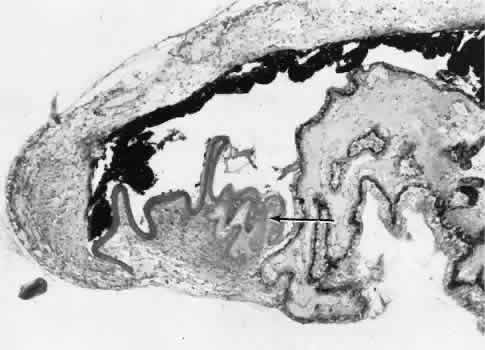

RETINAL HEALING

Wound healing of the neurosensory retina follows the principles of wound healing. There is an initial removal of all necrotic tissue by phagocytosis followed by proliferation of cells to form a chorioretinal bond. The healing, however, is modified in most instances by the lack of participation by the blood vessels.43–45 Astrocytes from the neurosensory retinaproliferate from the peripheral viable tissue into the wound and downward into the area of the subretinal space (Fig. 12). Retinal pigment epithelial cells from the peripheral viable tissue undergo fibrous metaplasia and proliferate upward into the area of the subretinal space. When the two proliferating cell types unite, a tight chorioretinal bond is formed. Increased retinal adhesiveness has been estimated to be 140% of the normal degree of adhesiveness 2 weeks after photocoagulation.46 Retinal holes may heal spontaneously if supported by an intact vitreous base or if located adjacent to the retinal pigment epithelium (Fig. 13).47,48 For the retinal pigment epithelium to differentiate, it must be in contact with overlying retinal pigment epithelium.49 Choriocapillaris repair from a photocoagulation wound of the retina appears to proceed in a manner similar to that of repair of capillary thrombosis in other tissues.50 The vascular repair process may not reproduce the lobular architecture of the native choriocapillaris.51 The choriocapillaris may regenerate in areas of restored retinal pigment epithelium.52 Proliferative vitreoretinopathy is an expression of abnormal retinal wound healing.53

Fig. 12. Light micrograph of an area over a retinal buckling element for retinal reattachment. Cryotherapy has been applied in the area, causing atrophy of the neurosensory elements of the retina. There is an intimate association of the remaining glial elements of the retina (R) with proliferated retinal pigment epithelial cells in the plane of the former subretinal space (arrow). The adhesion prevents intraretinal separation in this area. (Periodic acid-Schiff stain; × 100.)